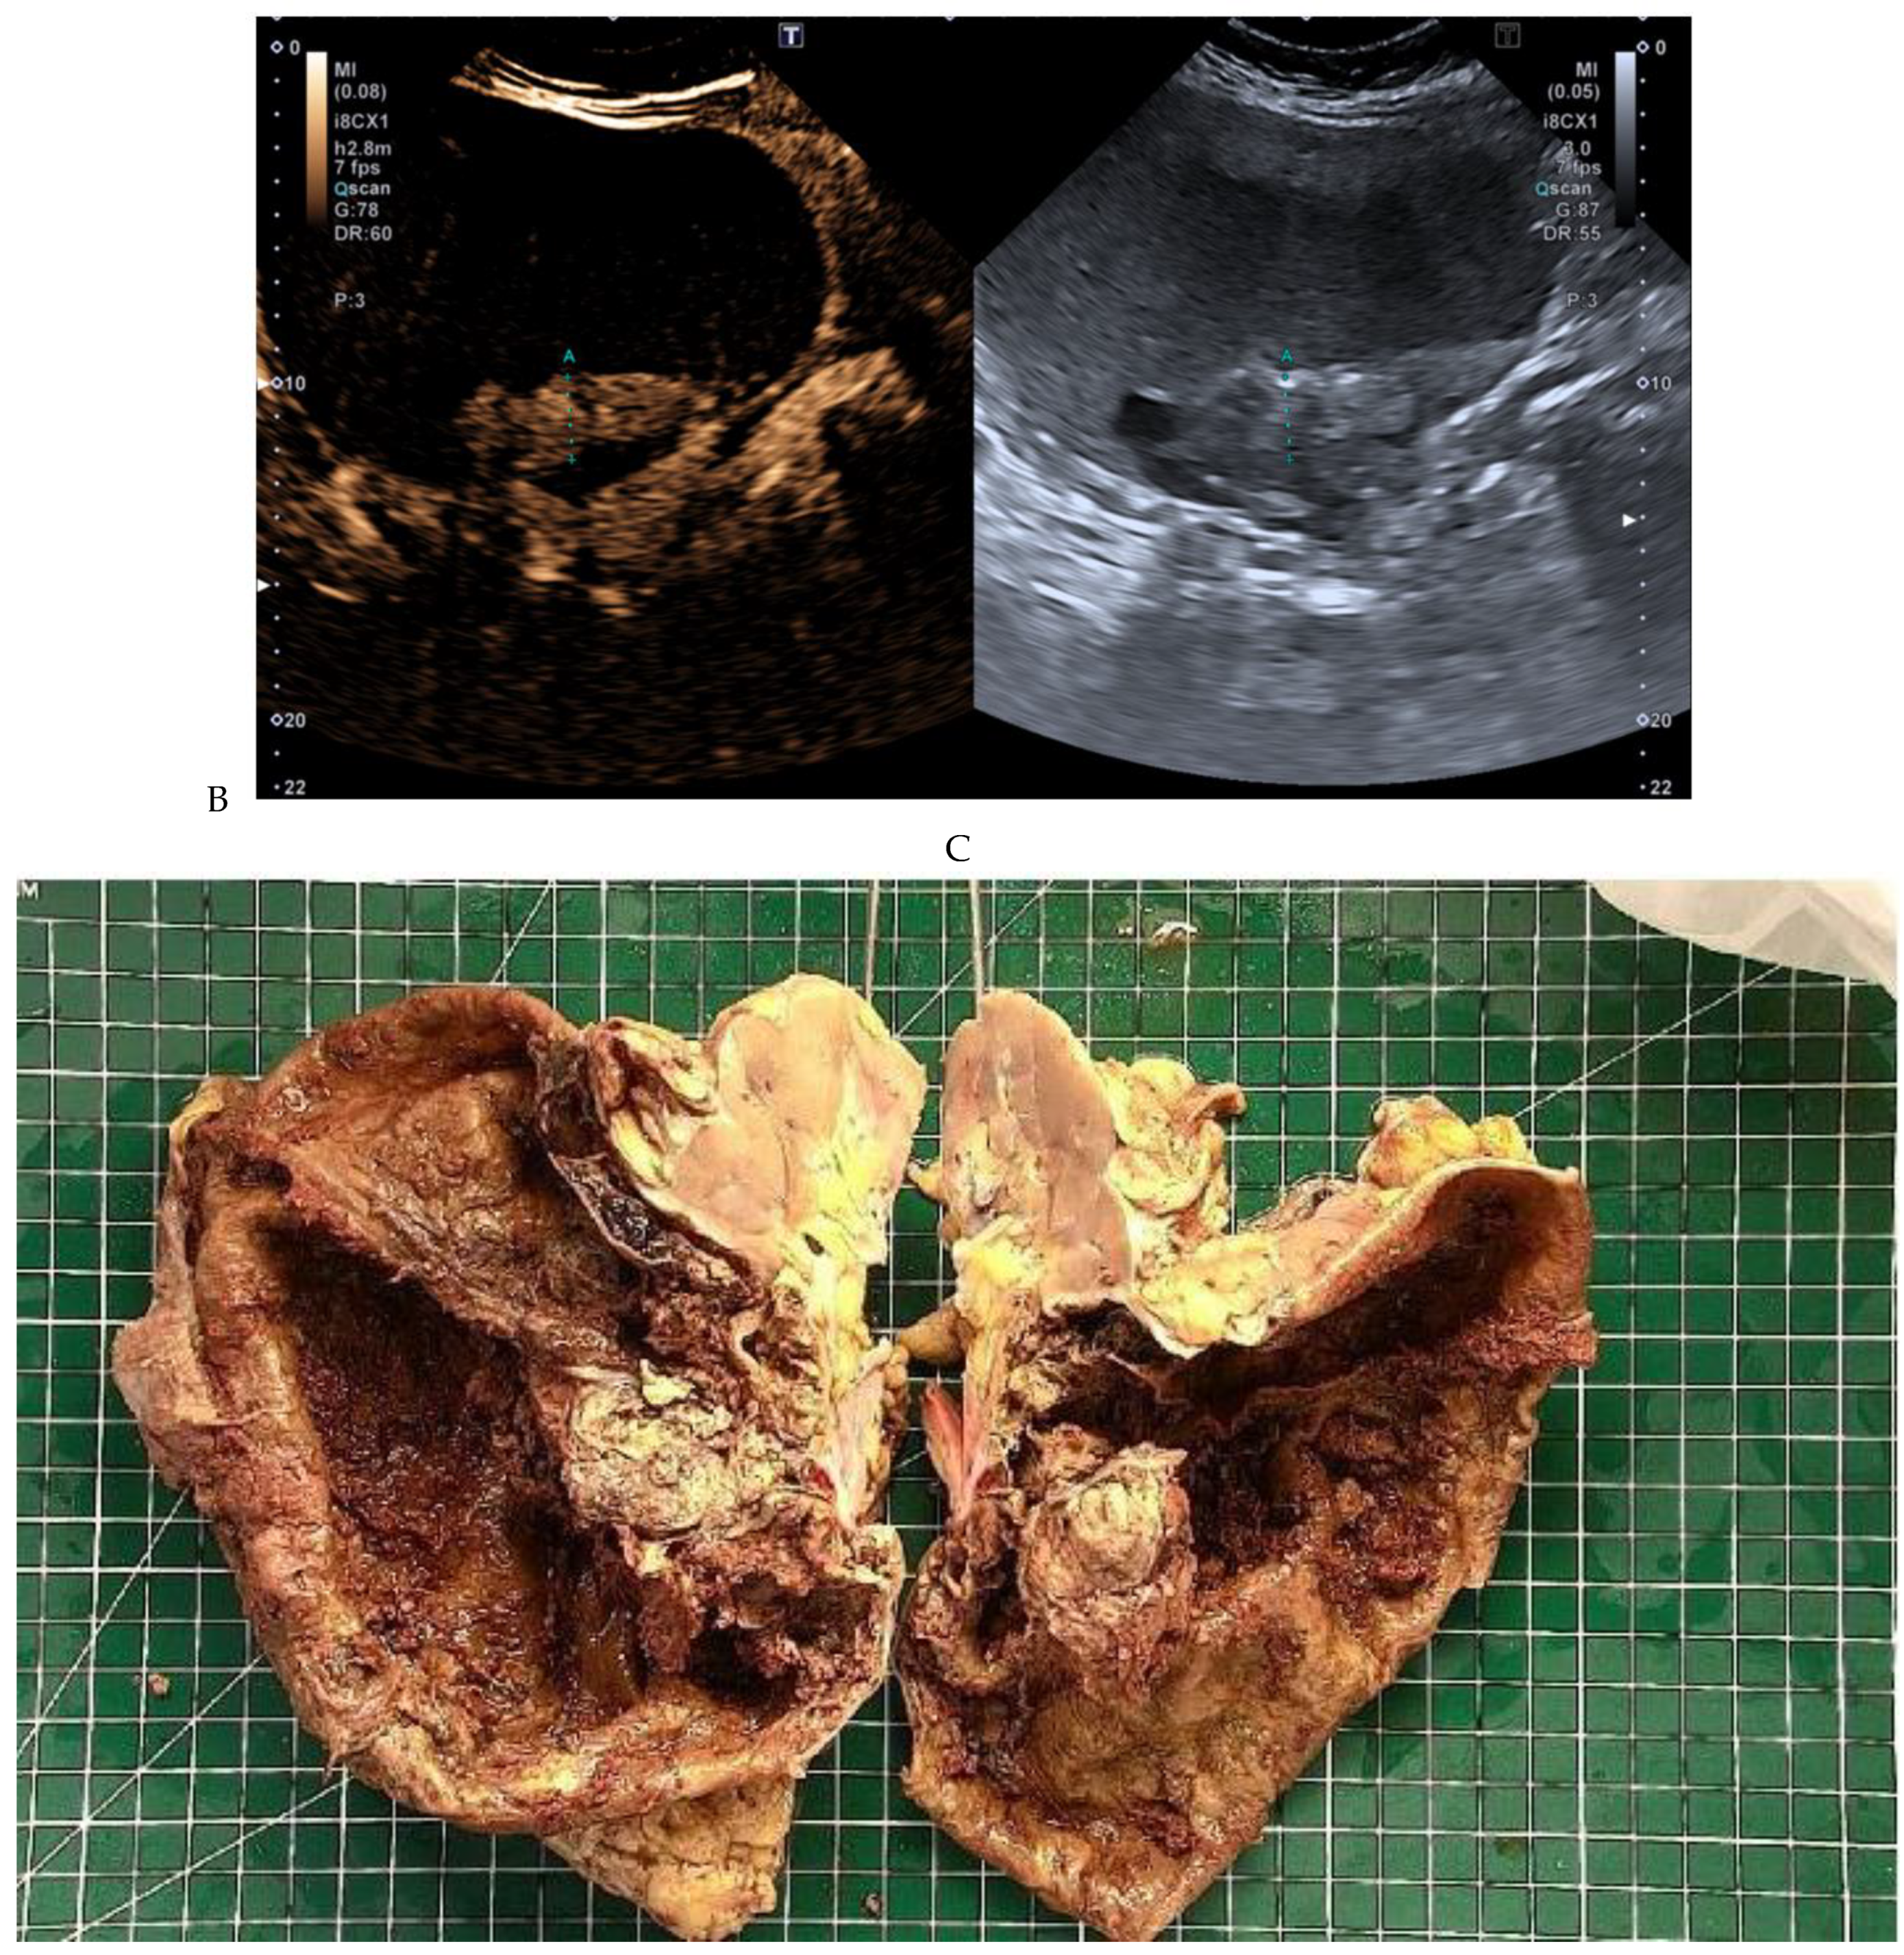

Figure 10.

Papillary renal cell carcinoma in the right kidney of a 54-year-old woman. (A) B-mode ultrasound shows a large right cystic renal mass with heterogeneous contents and a dependent sediment. (B) CEUS with Sonovue® (Bracco Imaging France, Massy, France) reveals the presence of a solid enhancing component at the posterior aspect of the mass. (C) The mass was resected. Pathology identified a necrotic papillary renal cell carcinoma. Courtesy of Pr S. Ferlicot, Department of Pathology, Bicêtre Hospital.

2.4. Contrast-Enhanced Ultrasound